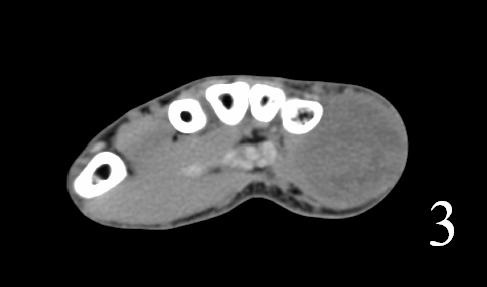

CT

- Shows a heterogeneous mass sometimes involving adjacent bone

- After contrast, the mass enhances (Fig. 2, Fig. 3)

- Hard to identify necrosis, hemorrhagic or calcification.

Fig. 2-3: Coronal and axial (Fig. 3) CT of a rhabdomyosarcoma of the hand shows a well circumscribed mass isointense to muscle